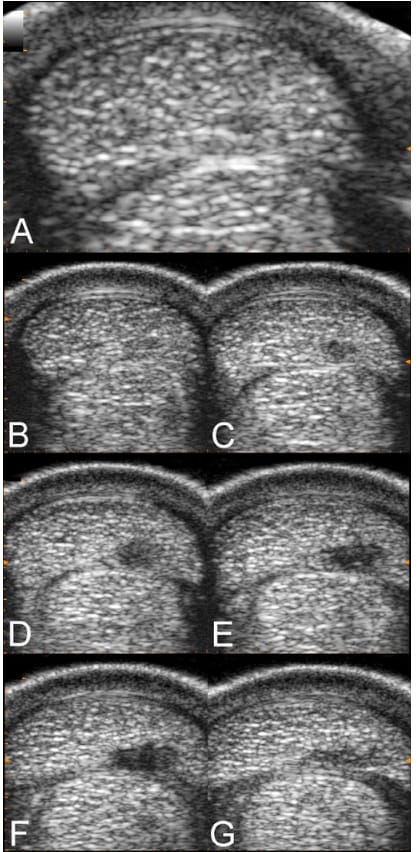

Ultrasonographic images of the left forelimb SDFT of a 3-year-old French Trotter after 4 months of training on a hard sand track. Image A, recorded at the midmetacarpus, is 1 of the 5 images in the transverse section used for the SDFT CSA measurement (methods illustrated in Figure 1). Images B through G, acquired with a lower magnification compared to image A, come from the ultrasonographic proximodistal screening performed to document the injury (independently from the CSA measurement). Images B and C are just proximal and distal (respectively) to the midmetacarpus level (where image A was recorded). Images B through G show that the maximal severity zone of the lesion is slightly distal (here, of 2 to 3 cm) to the CSA measurement site.